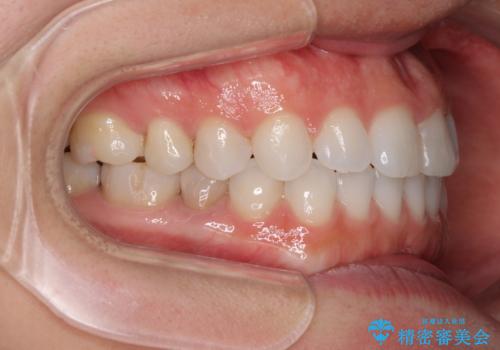

- 上下の前歯の反対咬合を気にして来院された患者様です。

インビザラインを用い、下顎はIPR(歯と歯の間を削る)と歯列全体を後方に移動させ、上顎は前歯を持ち上げることで、反対咬合を改善していくこととしました。

インビザラインによる反対咬合の改善は、上の歯が下の歯を乗り越えていく期間に咬み合わせが非常に不安定となり、治療が長期化することがあります。

こちらの患者様も、一時的に前歯でしか咬めない時期がありましたが、比較的早く咬み合わせが安定し、1年ほどで治療を終えることができました。